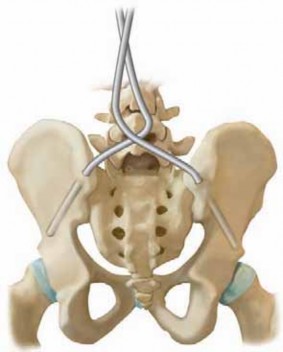

3. The curve patterns of neuromuscular scoliosis are most commonly lumbar or thoracolumbar with associated pelvic obliquity (

FIG 1

).

FIG 1•

Typical neuromuscular curve pattern in a child with quadriplegic-pattern cerebral palsy.

A.

Radiograph of long thoracolumbar curve with pelvic obliquity.

B.

Clinical picture of this child with poor sitting balance.